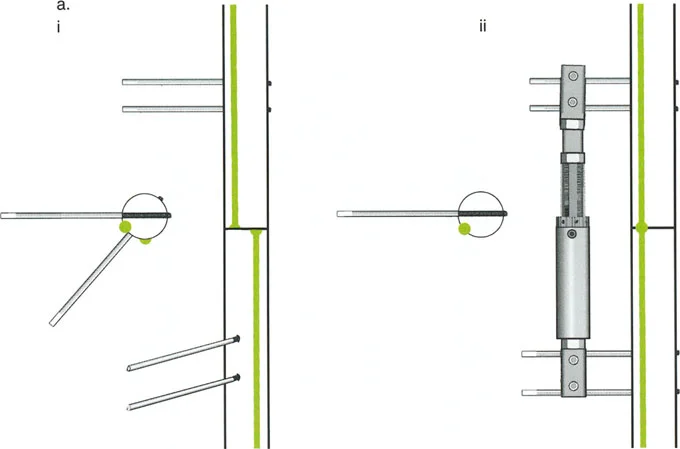

ومع ذلك، تعتمد هذه "المعجزة البيولوجية" بشكل كبير على الاستقرار الميكانيكي. إذا كان المثبت الخارجي شديد الصلابة، فقد لا يتكون العظم الجديد بشكل كافٍ؛ وإذا كان فضفاضًا جدًا، فإن قوى القص ستدمر الأوعية الدموية الدقيقة التي تتشكل في الفجوة، مما يؤدي إلى تكوين غضروف ليفي وعدم التحام العظم. يجب أن يوفر الجهاز حركة محورية دقيقة مع منع قوى القص وعدم الاستقرار الدوراني بشكل صارم.

قيود الأسلاك والدبابيس في القاعدة 2

لتحقيق هذه الترجمة الضرورية والمقصودة بسلاسة باستخدام إطار دائري كامل الأسلاك، يلزم استخدام أسلاك الزيتون المعاكسة (counter-opposed olive wires). تعمل أسلاك الزيتون كقوى سحب ديناميكية، تسحب قطعة العظم على طول الحلقة أثناء فتح المفصلات. بدون أسلاك الزيتون، سيبقى العظم ثابتًا بينما تتحرك الحلقة عبر الأنسجة الرخوة، مما يسبب نخرًا شديدًا في الجلد.

على العكس من ذلك، إذا تم استخدام دبابيس نصفية (مسامير شانز)، فإنها تقيد العظم بطبيعتها بالحلقة. نظرًا لأن الدبابيس النصفية هي أذرع صلبة (مثبتة من طرف واحد بالحلقة ومغروسة في العظم من الطرف الآخر)، فإنها لا تسمح للعظم بالانزلاق على طول محور السلك. هذا يجعل أسلاك الزيتون غير ضرورية للترجمة في منشآت الدبابيس النصفية، ولكنه يتطلب من الجراح التأكد من أن الدبابيس النصفية قوية بما يكفي (عادةً دبابيس بقطر 5 مم أو 6 مم مطلية بهيدروكسي أباتيت) لتحمل لحظات الانحناء الناتجة عن الترجمة.